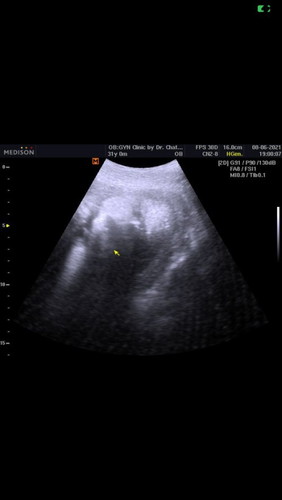

พอ37w2dแตกแล้วจร้า. ได้ลูกสาว.

ชื่อ ด.ญ.ปุณยนุช. แสนสิงห์ ชื่อเล่น. น้องหมูน้อยแก้มใส เกิดวันอังคาร ที่13 กค 2564. นน 2,640g. เด็กเล็กพริกขี้หนูของแม่. จิ๋วแต่แจ๋ว. ที่แข็งแรงมากๆ ผ่านการตรวจทุกอย่าง คลอดง่าย. ไม่ทำให้แม่เจ็บนาน แม้จะคลอดก่อนกำหนด ตั้ง3สัปดาห์ กำหนดคลอด 2สค64 แม้จะคลอดก่อนกำหนดคลอด. แต่ !!!หนู ผ่านการตรวจทุกอย่าง ตัวไม่เหลือง ไม่ต้องอบ นน ก็ผ่าน.#ท้องแรกคะ น้ำเดิน20.05 นาที. ถึง รพ. ราวๆ20.40นาที ทำประวัติ ส่งตัวเข้าห้องรอคลอด ราวๆ21.08วัดปากมดลูก ขยาย 2.6เซ็น ผ่านไป ราวๆ1ชมเศษ เวลา 23.50 ปากมดลูกขยาย เป็น 9เซ็น คลอด 23.52 นาที. แอบวิตกกังวลว่าน้องจะเป็นอะไร. เพราะพยาบาลตรวจปากมดลูก ก่อนจะคลอดบอกน้ำแห้งมาก. แล้วขณะคลอดได้ยิน เจ้าหน้าที่คุยกันว่า รกพันคอลูก. กังวลมาก. ว่าจะลูกจะปลอดภัยรึเปล่า. แต่ก็อึดใจเดียวเบ่ง 3ครั้ง. คลอดแล้ว. แม่ลูก แข็งแรง มาก